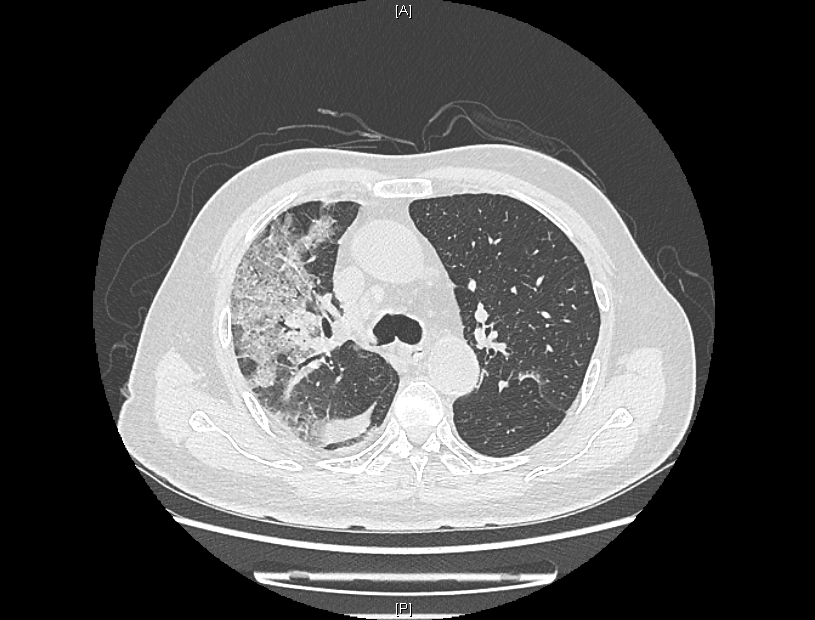

来院时,患者感染新冠病毒5天,持续发烧不退,出现了憋气、意识不清。患者入院后,经过医院持续监察发现,患者肺部CT逐步呈“白肺”状态,血气氧分压一度降至50mmHg,“正常血气氧分压为80-100mmHg,低于60mmHg,在临床上就可诊断为I型呼吸衰竭。”感染性疾病科主任林明贵说。

患者肺部CT检查图像

针对患者情况,医院对症施策,全力以赴做好患者的救治工作。感染性疾病科立即为患者行无创呼吸机支持,首要改善呼吸状况。针对肺部病变,团队应用激素减轻肺部渗出,改善炎症,促进病灶吸收,并给予抗病毒药物;针对血液降钙素原检查发现患者合并细菌感染,及时给予抗生素治疗;针对重症患者急转直下的病情,科室医护团队密切医疗监测,强化查房,发现问题及时调整。

在多学科联合保驾之下,老人入院后5天病情出现了转机,成功解除无创呼吸机,并逐步从高流量吸氧降至经鼻导管吸氧。“当时看到肺部影像时,心已经凉了半截,做好了最坏的思想打算。”患者的儿子说,老人生病前爱好打乒乓球,希望此次康复后,重新回归他热爱的球场。